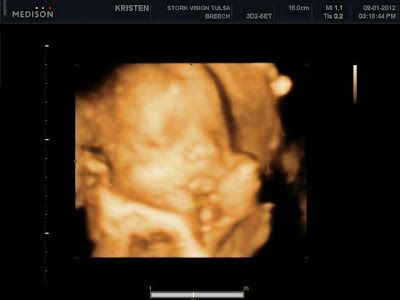

HELLO 3rd trimester - I can not believe you are already here!!  I'm getting used to being back to work and I'm not feeling as tired as I was last week. :)  Let me just add that I am absolutely loving my job!!!  I love teaching 6th grade so much... the kids are soo sweet and I feel like it's my true calling.  I also love my new teaching partner and we are doing some really fun things in science!  I'm not so much loving leaving my sweet baby at home but at least he stays at our house with my mom.  I mean, it really could not get any better!!  I am beyond appreciative of all she does for us! :)  The most exciting part of this past week was our 4D ultrasound... We LOVED getting to see little Harrison!!  He's cute as can be and looks a lot like his handsome brother in some of the pics.  When we were watching him on the screen we both thought he looked a lot like me but then when you look at his pics next to C's 4D, they really have a lot of similarities!  My next doctors appointment is Monday and I have to get a Rhogam shot - not looking forward to it at all.  I hate shots, a whole lot, but I am Rh negative and it is most definitely worth it for the baby!!  I guess this is my last appointment before the more frequent visits start.  Hard to believe.

Sweet little legs

Profile

Harrison on the left, Christian on the right.... What do you think??